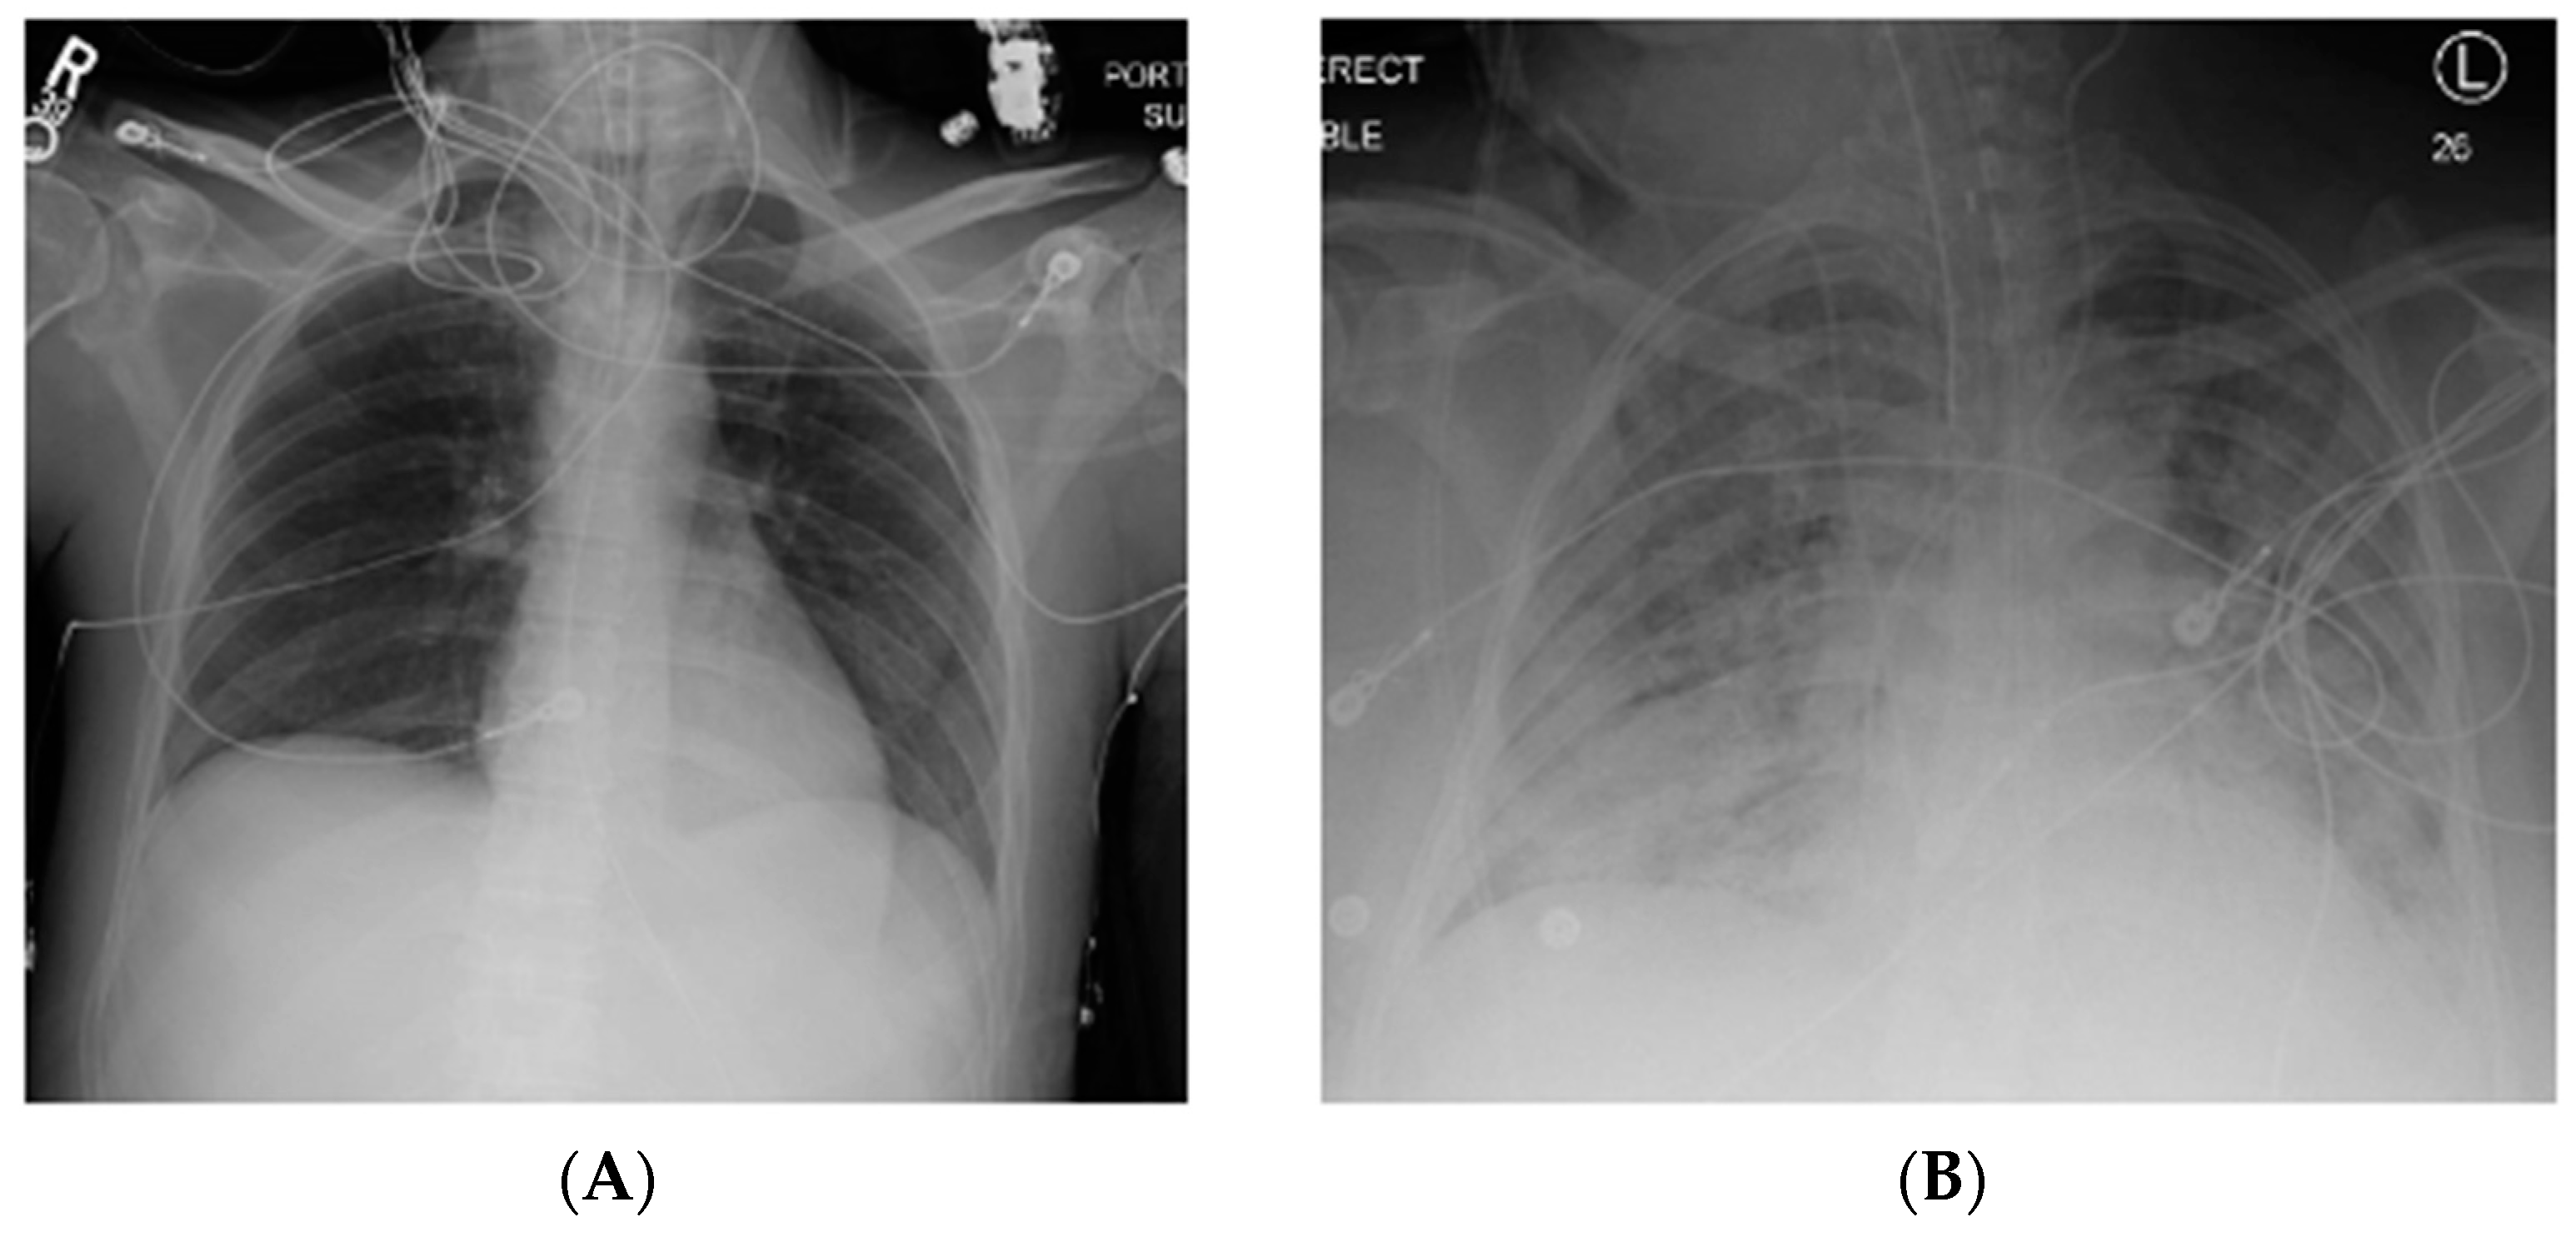

| Imaging | Bilateral opacities noted on either CXR or CT scan that are not otherwise explained by fluid overload or cardiac failure |